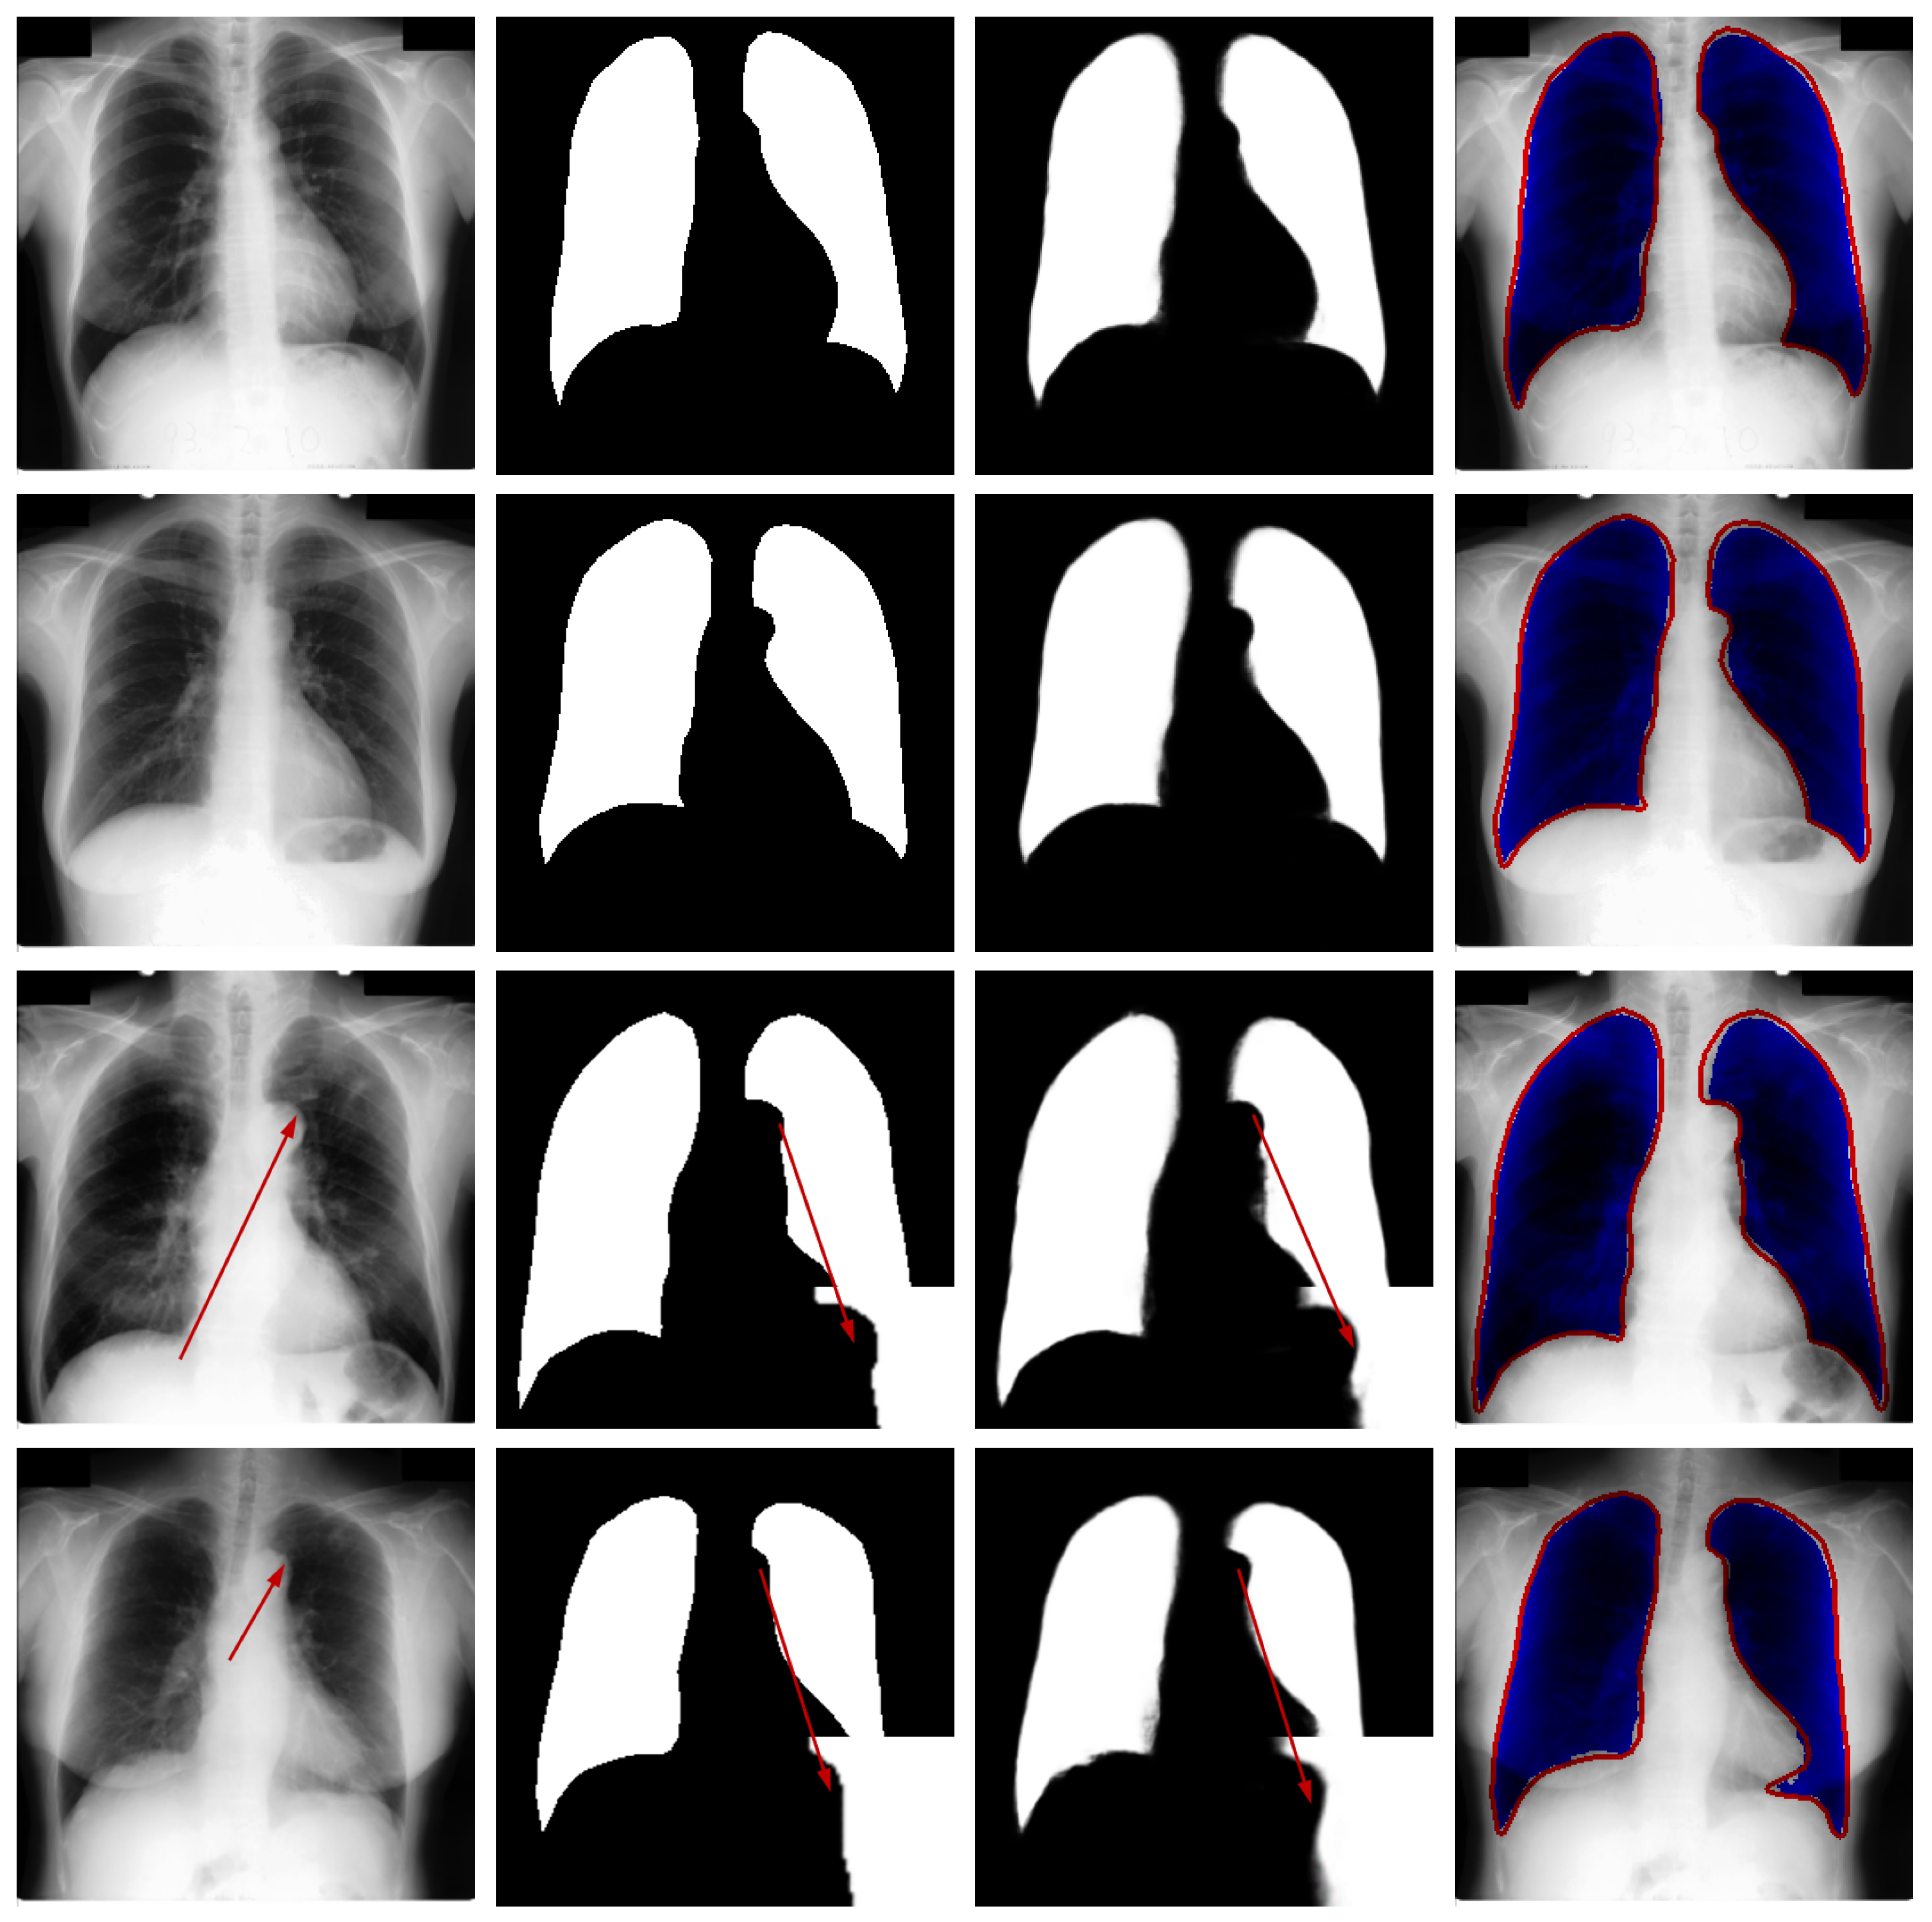

Qualitative Analysis: Figure 6 presents qualitative results from the JSRT dataset to visually assess the segmentation performance. The visualization includes test images, corresponding ground truth, model predictions, and difference maps for comparative analysis.

Figure 6.

Qualitative segmentation results on sample test cases. From left to right: original image from the test dataset, corresponding ground-truth mask, segmentation result generated by the proposed model, and difference map between the ground truth and prediction. The red arrows in the third and fourth rows of the first column in the figure represent difficult recognition areas, the red arrows in the second column represent corresponding ground truth image edge areas, and the red arrows in the third column represent difficult recognition edges in the predicted image. The blue area in the fourth column represents the predicted areas, and the red part represents the ground truth contour.

Visual inspection confirms that the proposed network generates lung masks with well-defined boundaries that closely align with anatomical structures. In most cases, the segmentation results show strong agreement with ground truth annotations, demonstrating the model’s capability to accurately identify pulmonary regions in CT images.

While the overall performance is satisfactory, certain challenging cases reveal limitations in boundary delineation, particularly in regions with low contrast or pathological alterations. These occasional discrepancies highlight opportunities for further refinement and suggest that clinical applications may benefit from optional manual correction in critical scenarios. The visual evidence thus validates the model’s effectiveness while acknowledging areas for future improvement.